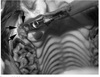

Figure 29-44. This intraoperative radiograph shows the punch correctly positioned over the affected apex and also shows that it is facing in a suitable direction to effectively remove this (09) cheek tooth.